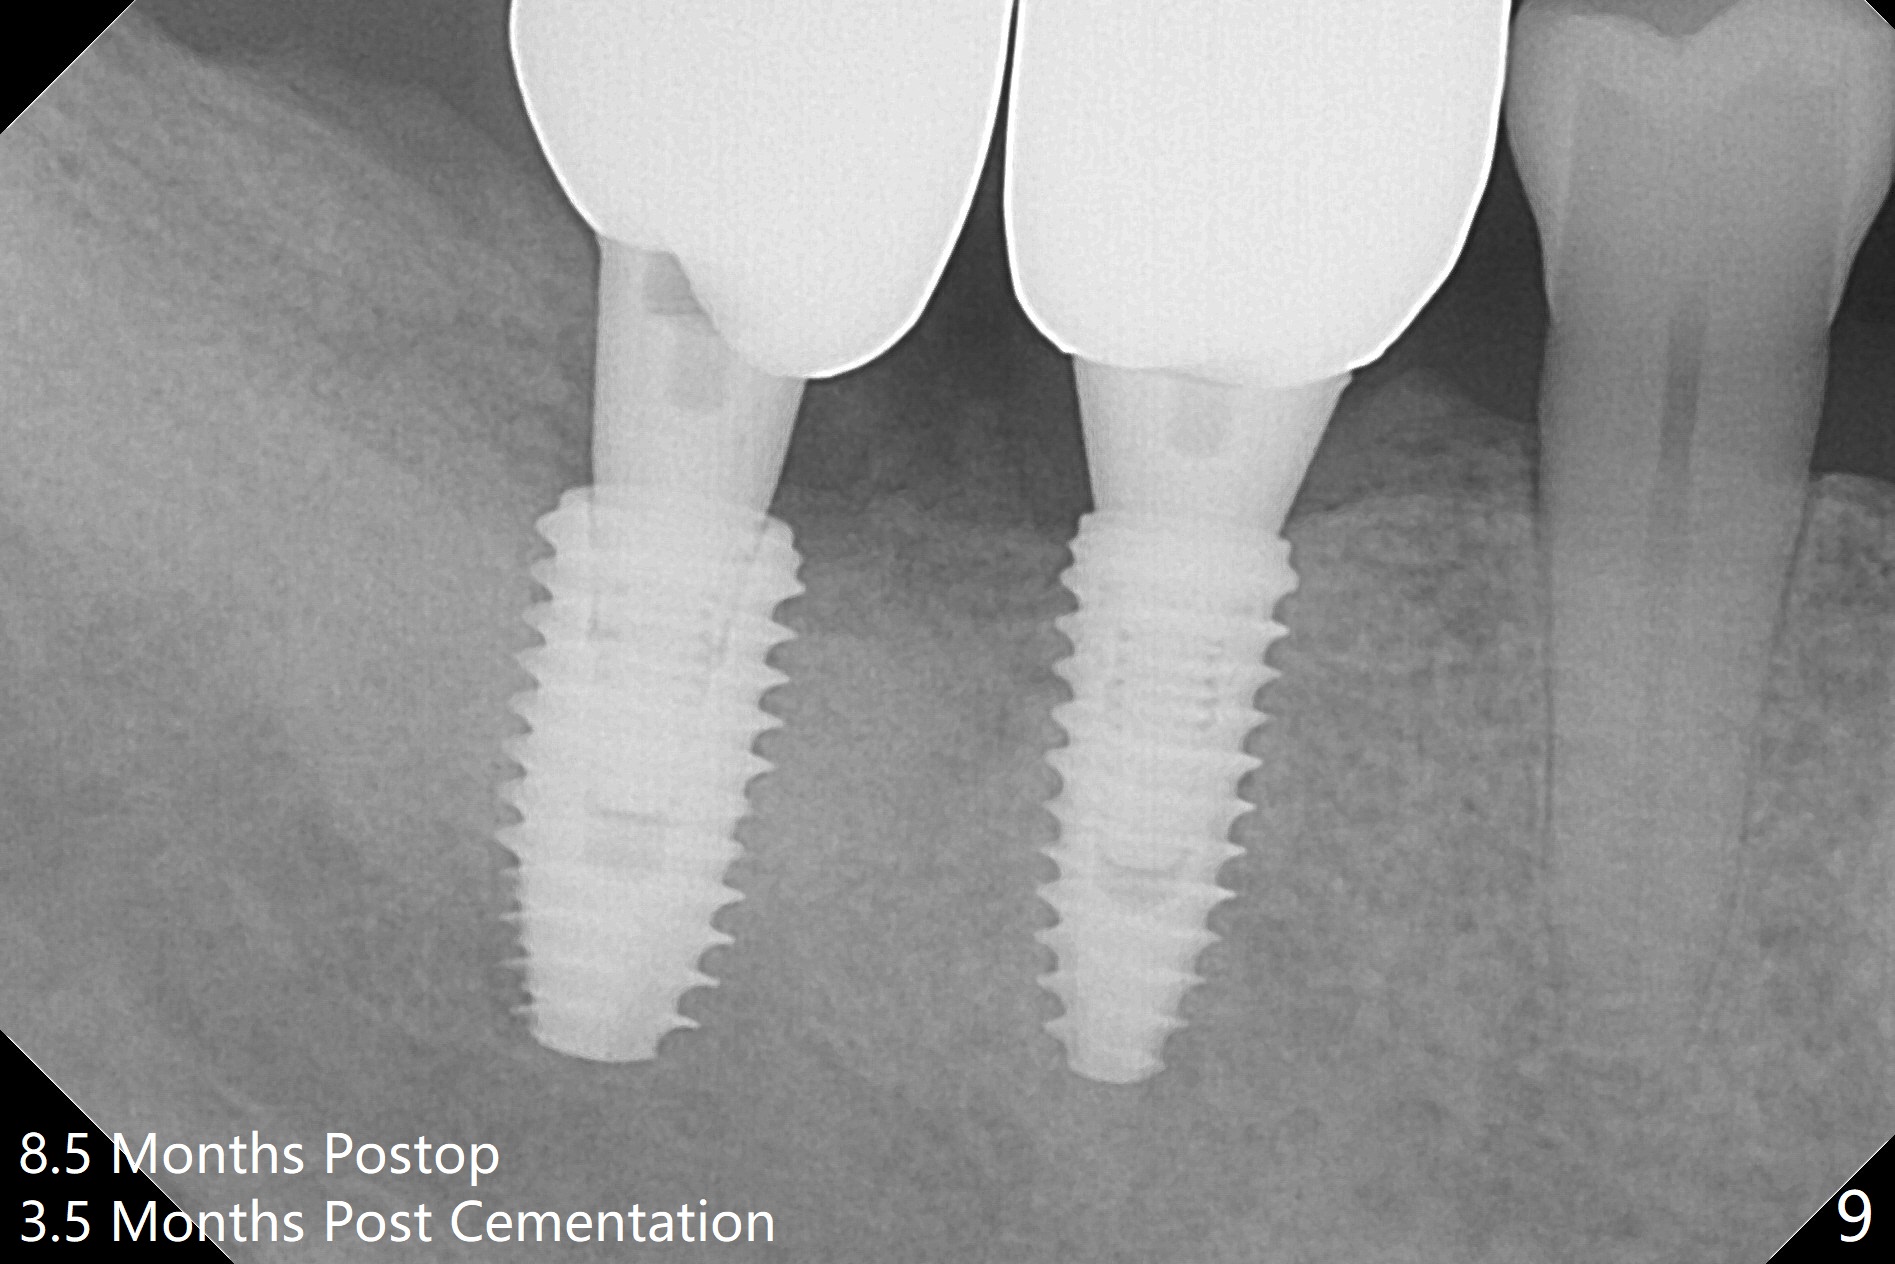

Osteotomy at the sites of #30 and 31 is initiated with Magic Split, followed by Magic Expanders (3.0 and 3.8 mm) at #31.  Initial depth of osteotomy is 13 mm with 2.2 mm drill (Fig.1).  After adjustment of the trajectory at #31 (Fig.1 arrow) and deepening the osteotomy by 2 mm, dummy implants are placed with stability (Fig.2).  Following increase in osteotomy at #31, the larger implant in fact loses stability (Fig.3).  The loose implant is pushed distal (Fig.4 arrow) with placement of autogenous bone mesial (*).  The stable implant at #30 (Fig.3) and its abutment (Fig.4) are used as a post to hold periodontal dressing, which covers the wound at #31 after placement of collagen plug and suturing.  In fact the same technique could be used when socket preservation was performed if an implant were placed at #30 at the same time.  When the periodontal dressing dislodges, the wound at #31 heals uneventfully (Fig.5,6).  The bone graft seems to remain in place 3 months postop (Fig.7).  The implant is uncovered with placement of a 6.8x7 mm healing abutment 4 months postop.  When a cementation abutment is placed and prepped, the buccal margin is much lower than the lingual (Fig.8 taken prior to cementation).  The patient enjoys mastication with the new implant crowns 3.5 months post cementation (Fig.9).